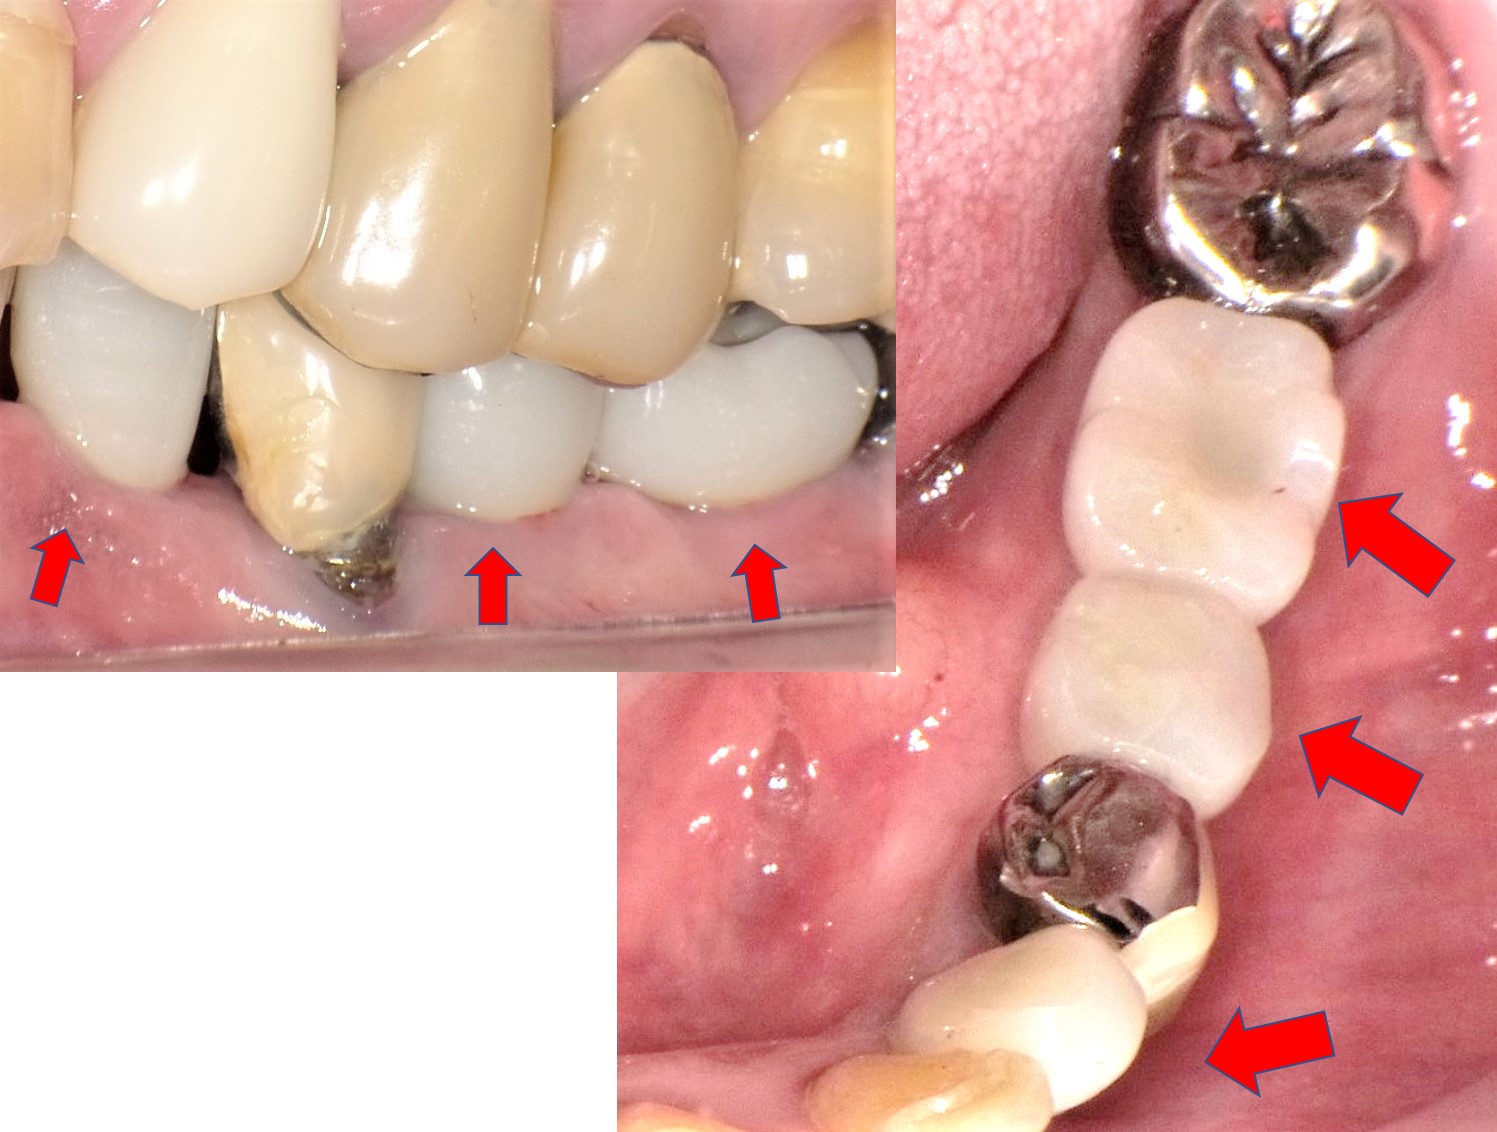

多数歯欠損にインプラントと入れ歯を併用した症例(歯が少ない,

多数歯欠損にインプラントと入れ歯を併用した症例(歯が少ない, 多数歯欠損ケース治療実績|実績・症例|朝霧 インプラント,

多数歯欠損ケース治療実績|実績・症例|朝霧 インプラント, 下顎多数歯欠損インプラント症例|症例解説|東京銀座シンタニ,

下顎多数歯欠損インプラント症例|症例解説|東京銀座シンタニ, 多数歯先欠・6歯以上の先天性部分無歯症の矯正治療,

多数歯先欠・6歯以上の先天性部分無歯症の矯正治療, 多数歯欠損ケース治療実績|実績・症例|朝霧 インプラント【書籍概要】本書は、インプラント治療に関する専門的な知識を提供することを目的とした書籍です。特に多数歯欠損や無歯顎症例に焦点を当て、実践的な治療法や症例を詳述しています。【著者情報】著者は、インプラント治療の分野で豊富な経験を持つ専門家たちで構成されています。彼らの知識と技術が詰まった一冊です。【対象読者】この書籍は、歯科医師や医療従事者、インプラント治療に関心のある方々に最適です。専門的な内容が多く含まれているため、実務に役立つ情報が得られます。- タイトル: MAXILLA-ORIENTED IMPLANTOLOGY- 著者: 林 裕幸, 武田 幸之, 桜井 幸弥, 森田 謙治- 出版社: ゼニス出版- 言語: 日本語- テーマ: 多数歯欠損・無歯顎症例のインプラント治療ご覧いただきありがとうございます。

多数歯欠損ケース治療実績|実績・症例|朝霧 インプラント【書籍概要】本書は、インプラント治療に関する専門的な知識を提供することを目的とした書籍です。特に多数歯欠損や無歯顎症例に焦点を当て、実践的な治療法や症例を詳述しています。【著者情報】著者は、インプラント治療の分野で豊富な経験を持つ専門家たちで構成されています。彼らの知識と技術が詰まった一冊です。【対象読者】この書籍は、歯科医師や医療従事者、インプラント治療に関心のある方々に最適です。専門的な内容が多く含まれているため、実務に役立つ情報が得られます。- タイトル: MAXILLA-ORIENTED IMPLANTOLOGY- 著者: 林 裕幸, 武田 幸之, 桜井 幸弥, 森田 謙治- 出版社: ゼニス出版- 言語: 日本語- テーマ: 多数歯欠損・無歯顎症例のインプラント治療ご覧いただきありがとうございます。